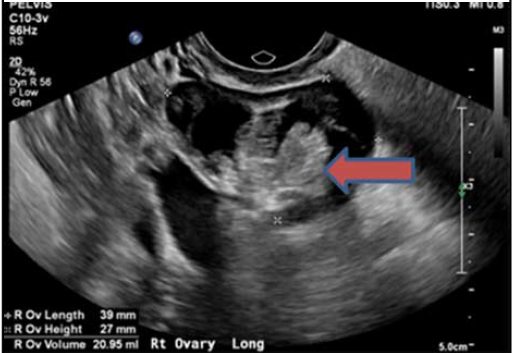

患者血清抗NMDA受体抗体回报阳性。且患者的盆腔超声及MRI提示右侧卵巢肿块,与囊性畸胎瘤表现一致。这些发现确认了抗NMDA受体脑炎的诊断。

图1 盆腔超声发现右侧卵巢肿物,符合囊性畸胎瘤表现